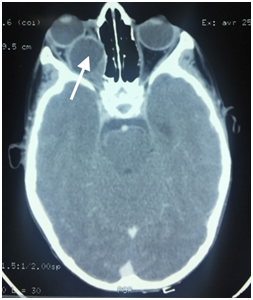

The rest of the clinical examination was normal.Orbital CT scan showed a well-defined cystic lesion,with distinct and regular border in the intraconal space of the right orbit (Figure 2).Based on CT scan finding, the age and the life-style of the patient, the presumptive diagnosis of orbital hydatid cyst was made.